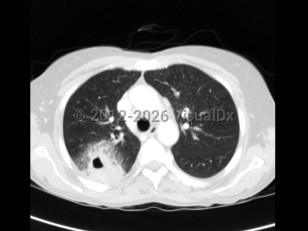

Fat emboliFat emboli